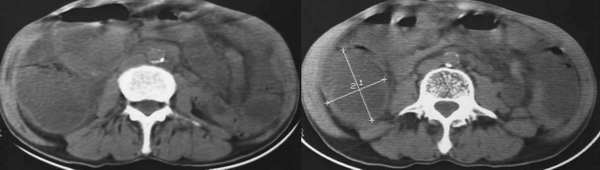

以下是引用lkc8963在2006-1-19 21:13:00的发言:[br]右半结肠及盆腔小肠明显积液扩张,腹腔内无明显渗出;右半结肠近端见多发点状高密度影;胆管内多发结石。[br]不知临床有哪些资料。本例需考虑胆石性肠梗阻的可能性,或胆系结石漏至结肠(异常通道如瘘)。